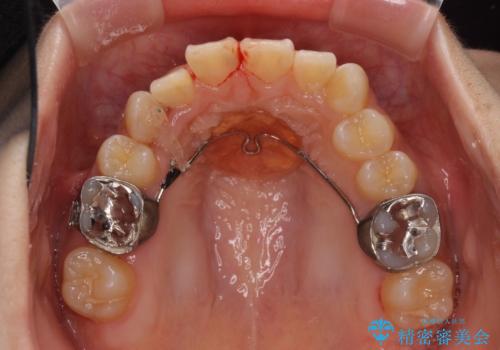

- 上下の八重歯を気にして来院された患者様です。

上下ともに八重歯の後ろの歯を1歯ずつ抜歯し、補助装置(リンガルアーチ)を用いて八重歯の位置を改善し、その後インビザラインにより矯正治療を行うこととしました。

途中海外留学をされたため、治療期間は長くなりましたが、事前に補助装置やワイヤー装置を併用したことで、きれいな歯列に仕上げることができました。